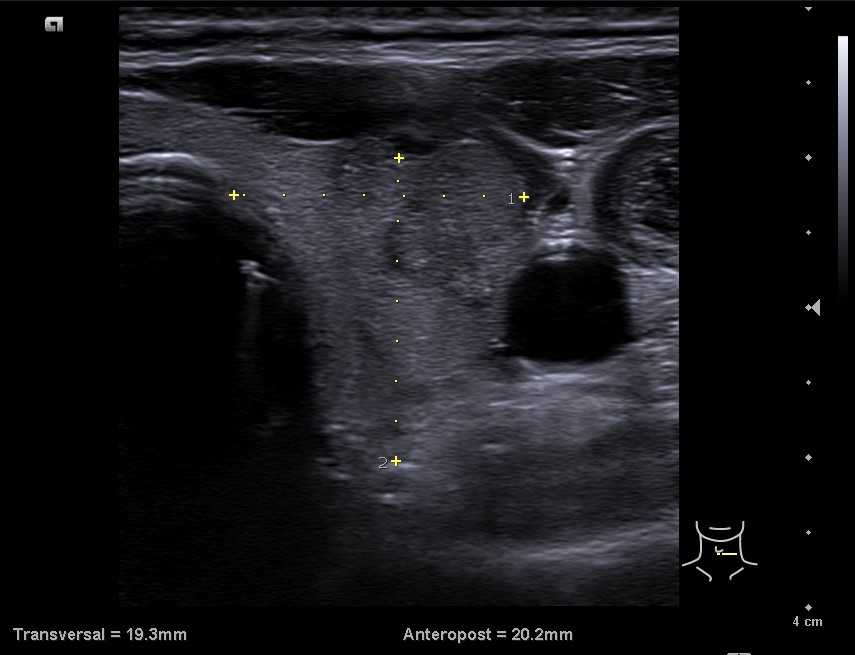

En la ecografía tiroidea se observa en LTI nódulo de 10 mm de bordes mal definidos, lobulado, mayormente sólido, más alto que ancho, isoecogénico, halo periférico hipoecoico, vascularización difusa, que sugiere TIRADS 5. Ausencia de flujo en Vena yugular interna izquierda, ensanchada, que sugiere trombosis yugular aguda o subaguda y junto a ella, posible conglomerado adenopático.